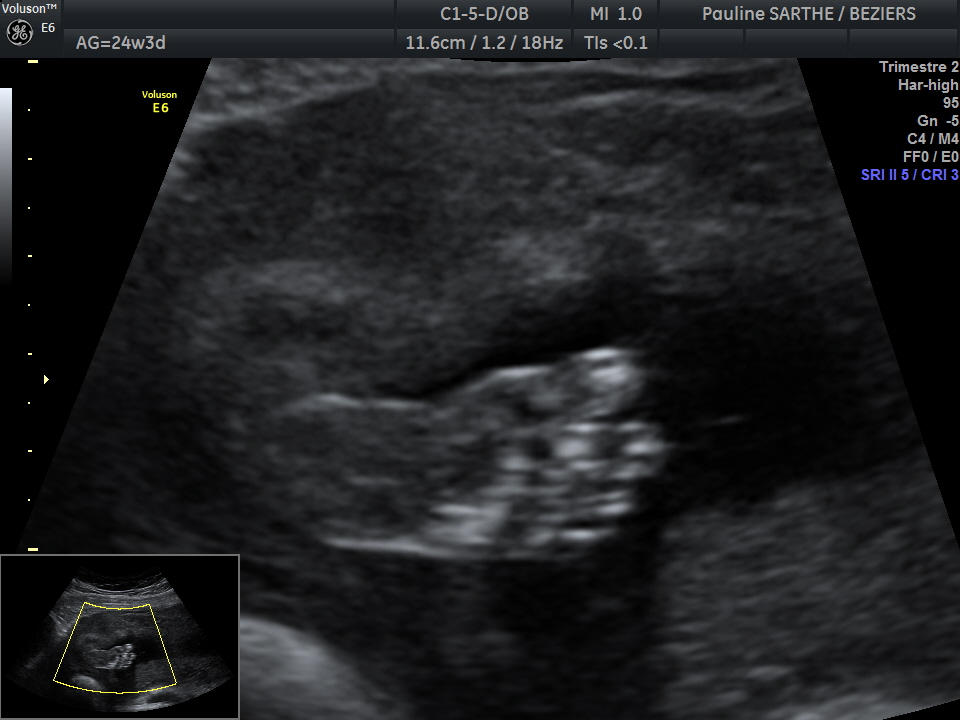

- l'échographie du 2 ème trimestre est réalisée entre 20 et 24 semaines d'aménorrhées (idéalement entre 21-23 semaines).Votre bébé a bien grandi et il est difficile de le visualiser en entier. C'est le moment idéal pour bien vérifier la vitalité de votre bébé à travers ses mouvements et le liquide amniotique , le bon développement de ses organes, sa croissance au travers des mesures de sa tête, de son périmètre abdominale et de son fémur qui permettront de donner une estimation de son poids ,et la localisation du placenta.

Si la position du bébé le permet, une visualisation en 3D vous permettra d’avoir une première image de son visage.